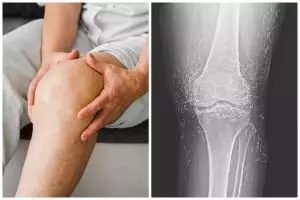

Bikin syok, dokter ini temukan benang susuk emas di lutut pasien saat lakukan rontgen